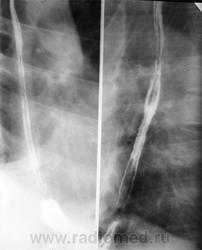

Процесс прохождения глотков бариевой взвеси (или специального бариевого препарата) регистрируют с помощью флюороскопии в реальном масштабе времени. Частое показание к рентгенологическому исследованию пищевода - диагностика желудочно-пищеводного рефлюкса. Он проявляется обратным забросом бариевой взвеси из желудка в пищевод при исследовании в горизонтальном положении или в положении Тренделенбурга. В случае обструкции пищевода инородным телом рентгенологическое исследование позволяет немедленно установить его уровень и выраженность. С помощью этого метода хорошо видны участки расширения и сужения пищевода при доброкачественных стриктурах (рубцовых, ахалазии). Для ахалазии характерно расширение проксимальной части пищевода и сужение его дистального отдела в форме «клюва». При опухолях пищевода (доброкачественных и злокачественных) виден дефект наполнения пищевода. Характерным признаком злокачественных образований (рака) является изъязвление слизистой и изменение ее рентгенологического рисунка, ригидность стенок пищевода, неровные контуры опухоли

Рентгенография и рентгеноскопия остаются важными методами диагностики доброкачественных и злокачественных опухолей желудка. Их дифференциальная диагностика основывается на анализе контуров опухоли, характера изменений складок желудка и локальной ригидности его стенок